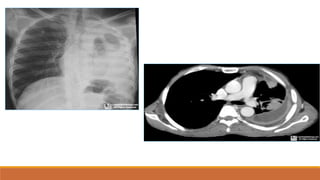

Độ xuyên

thấu tia

-

T

h

ấ

yđ

ược cột sống,

mạch máu sau bóng

tim